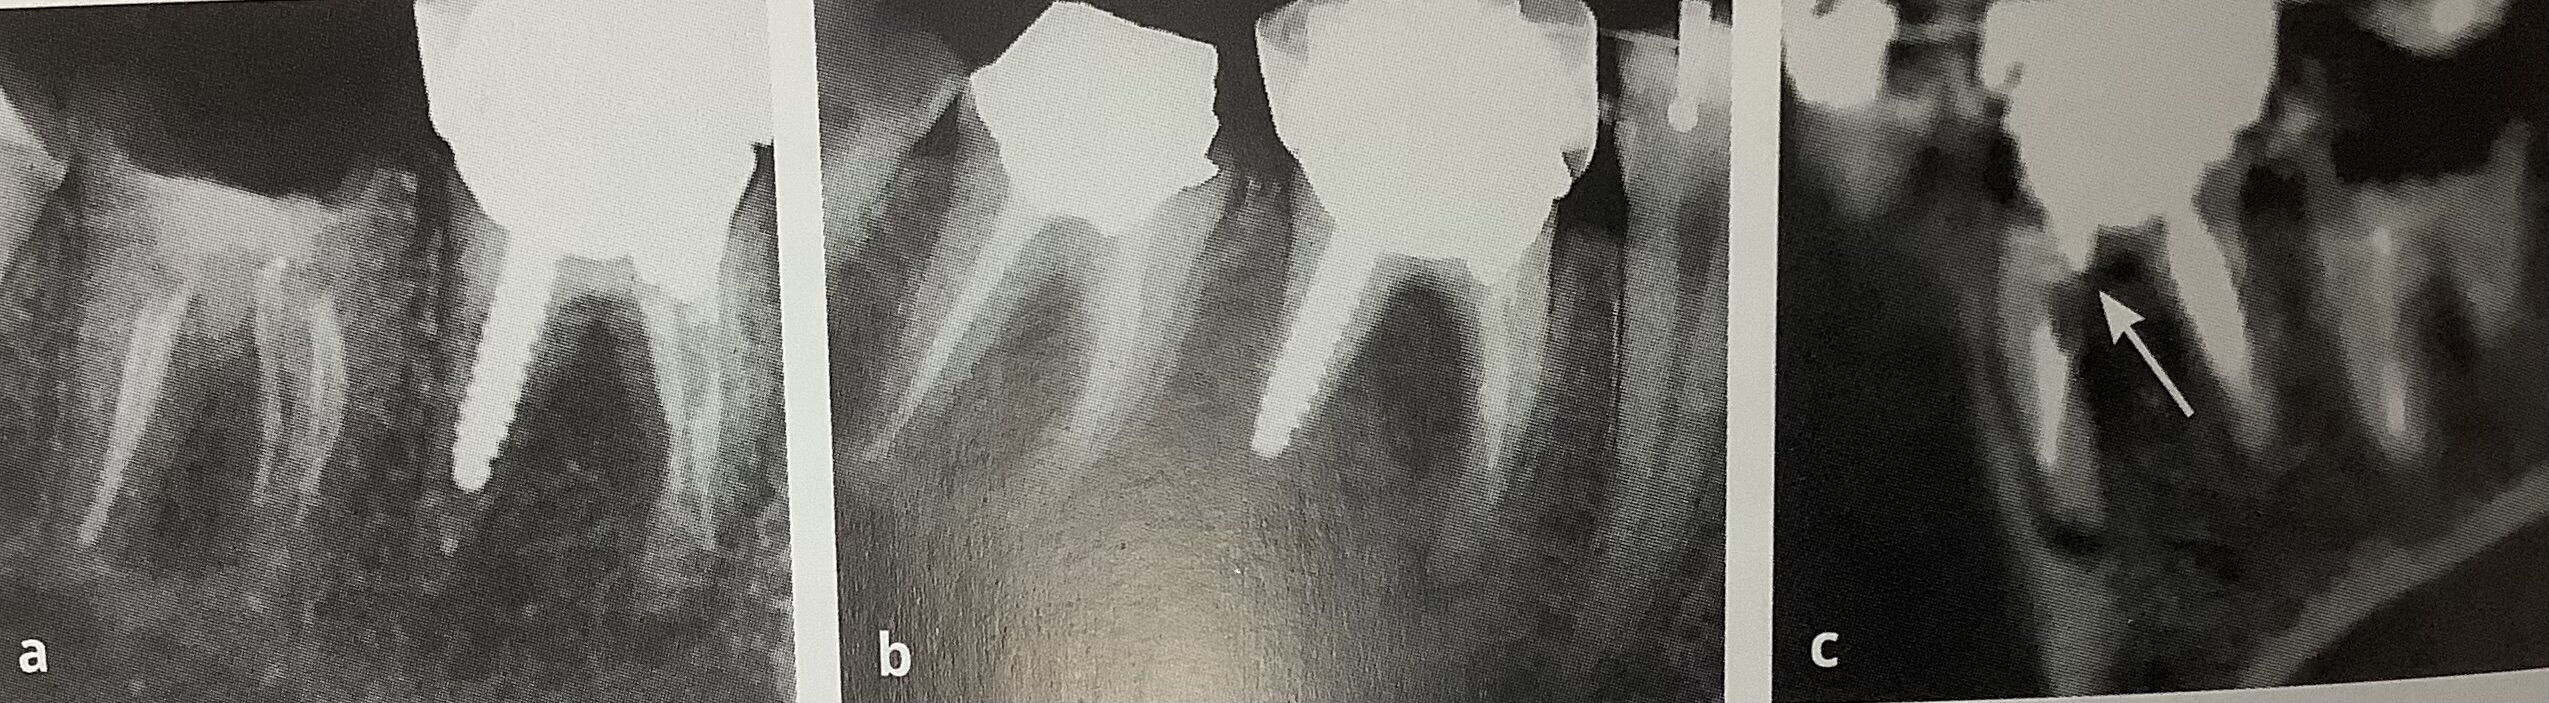

左と真ん中がいつものレントゲンで、

右がCTです。

被せ物の根っこの分かれ目,

ウチマタ部分が真っ黒です。

CTで見ると穴が開いてます。

ここはくぼんでいて、薄いので危険なんです。